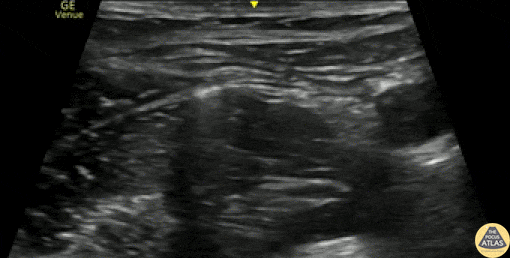

A 20s F was brought in by ambulance after she was struck by a vehicle. She had an obvious closed deformity to her thigh. Initial trauma workup was negative for other injuries, she remained awake/alert and hemodynamically stable, and was neurovascularly intact distally. After orthopedic consultation, a fascia iliaca nerve block was performed for analgesia in preparation for distal femur traction pin placement. The needle here enters from left of screen (lateral), injecting anesthetic just deep to the fascia iliaca, and spreading adjacent to the femoral nerve, which is seen to the left of (lateral to) the pulsating femoral artery. The patient had improvement of her pain, traction pinning was performed, and she was admitted for surgery. Dr. Arian Anderson, PGY4 Denver Health Residency in Emergency Medicine